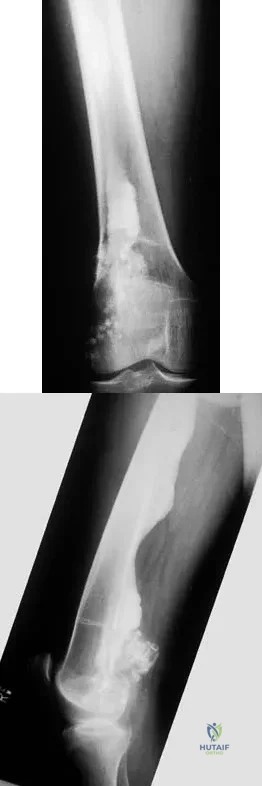

Question 94

What is the primary mechanism of injury for the fracture shown in Figures 33a and 33b?

Explanation